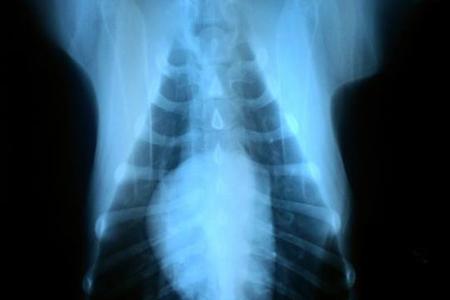

X rays of the heart and lungs.

X ray images can check for changes to the heart and blood vessels which are often enlarged when the dog has lots of heartworms. Garner breaks the news to an anxious oscar that he has tested positive for heartworms but re assures him that they are treatable. Oscars heartworm x ray heartwormdocs.

This is because dogs are natural hosts for heartworms parasites that can cause significant health problems for your. The parasites tend to occupy the right hand side of the heart and lungs and the organs will be bloated in this pattern as a result. X rays of dogs with heavy infestations will show enlargement of the right ventricle andor pulmonary arteries.